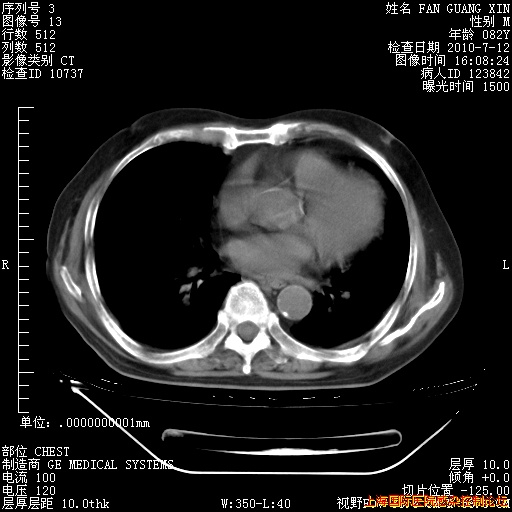

6月12日纵膈窗

今天复查CT

今天CT

整整相隔30天的肺部CT好像有所好转啊。甲强龙减量第3天,需要观察体温。